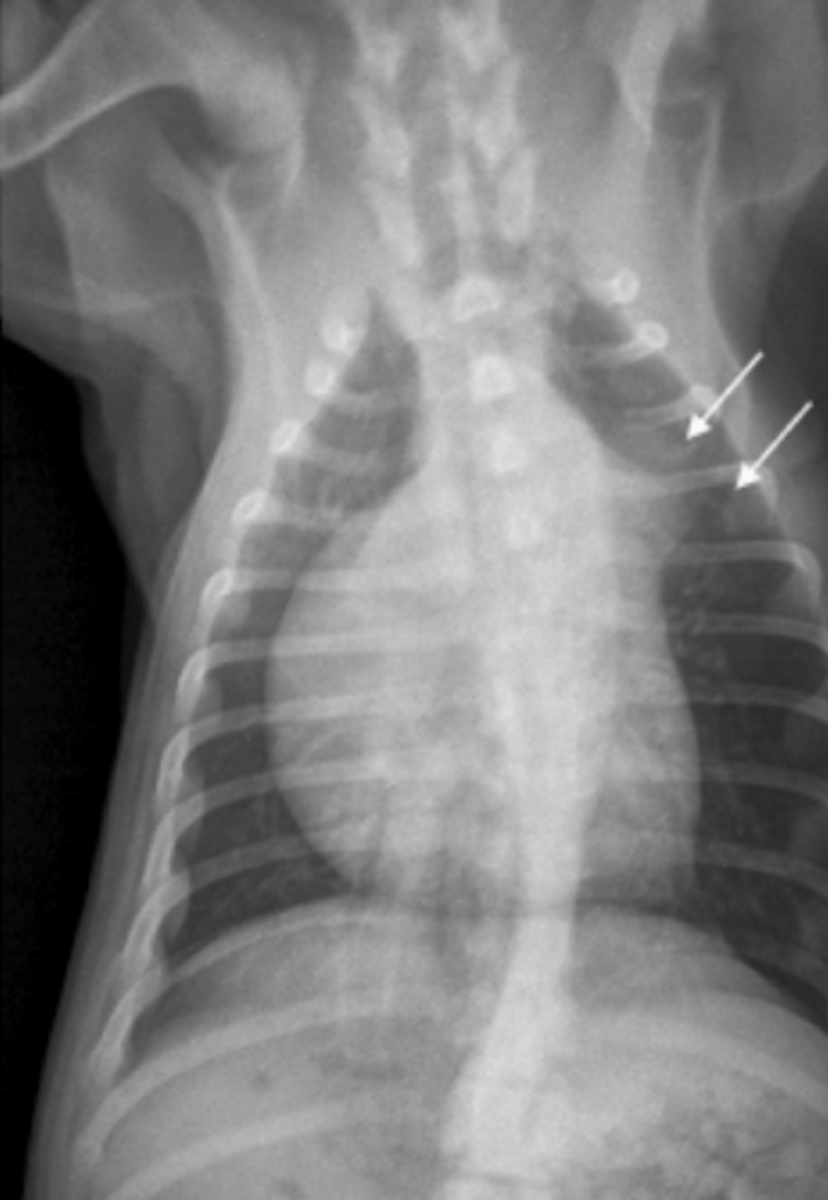

megaesófago

patología:

megaesófago, por cuerpo extraño

neumonía por aspiración por

la parenquíma pulmonar, por riesgo de neumonía por aspiración

si vemos megaesófago en una radiografía, es importante evaluar: